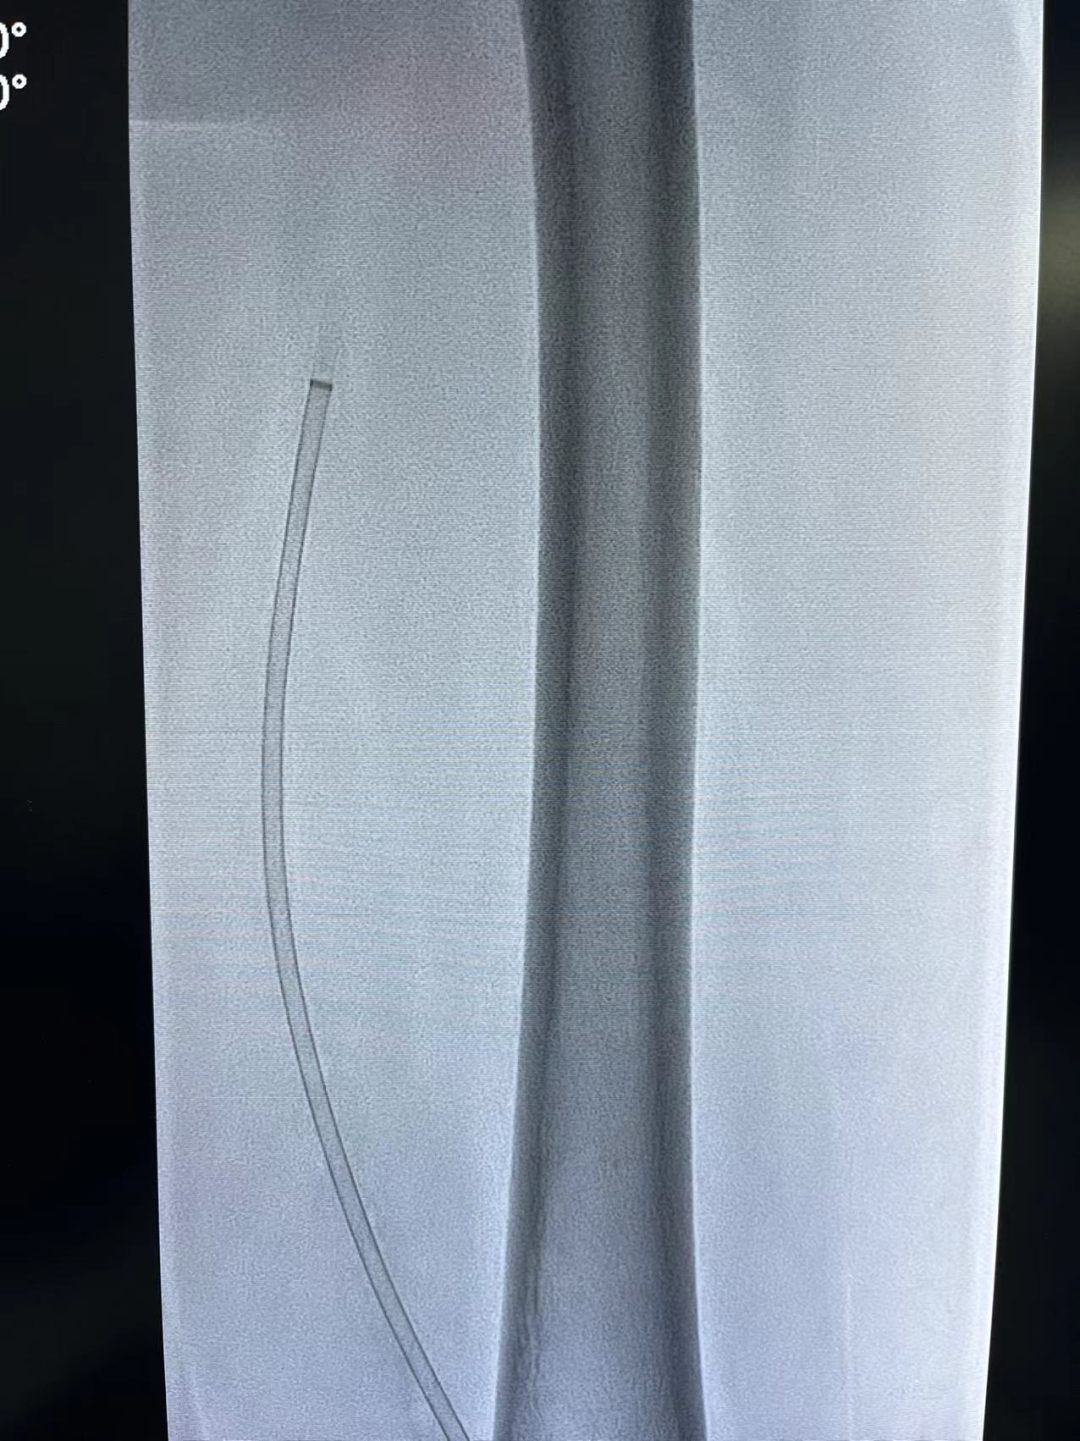

血栓清除以后,再次造影:股静脉血流恢复通畅。患者下肢肿胀症状立刻缓解。